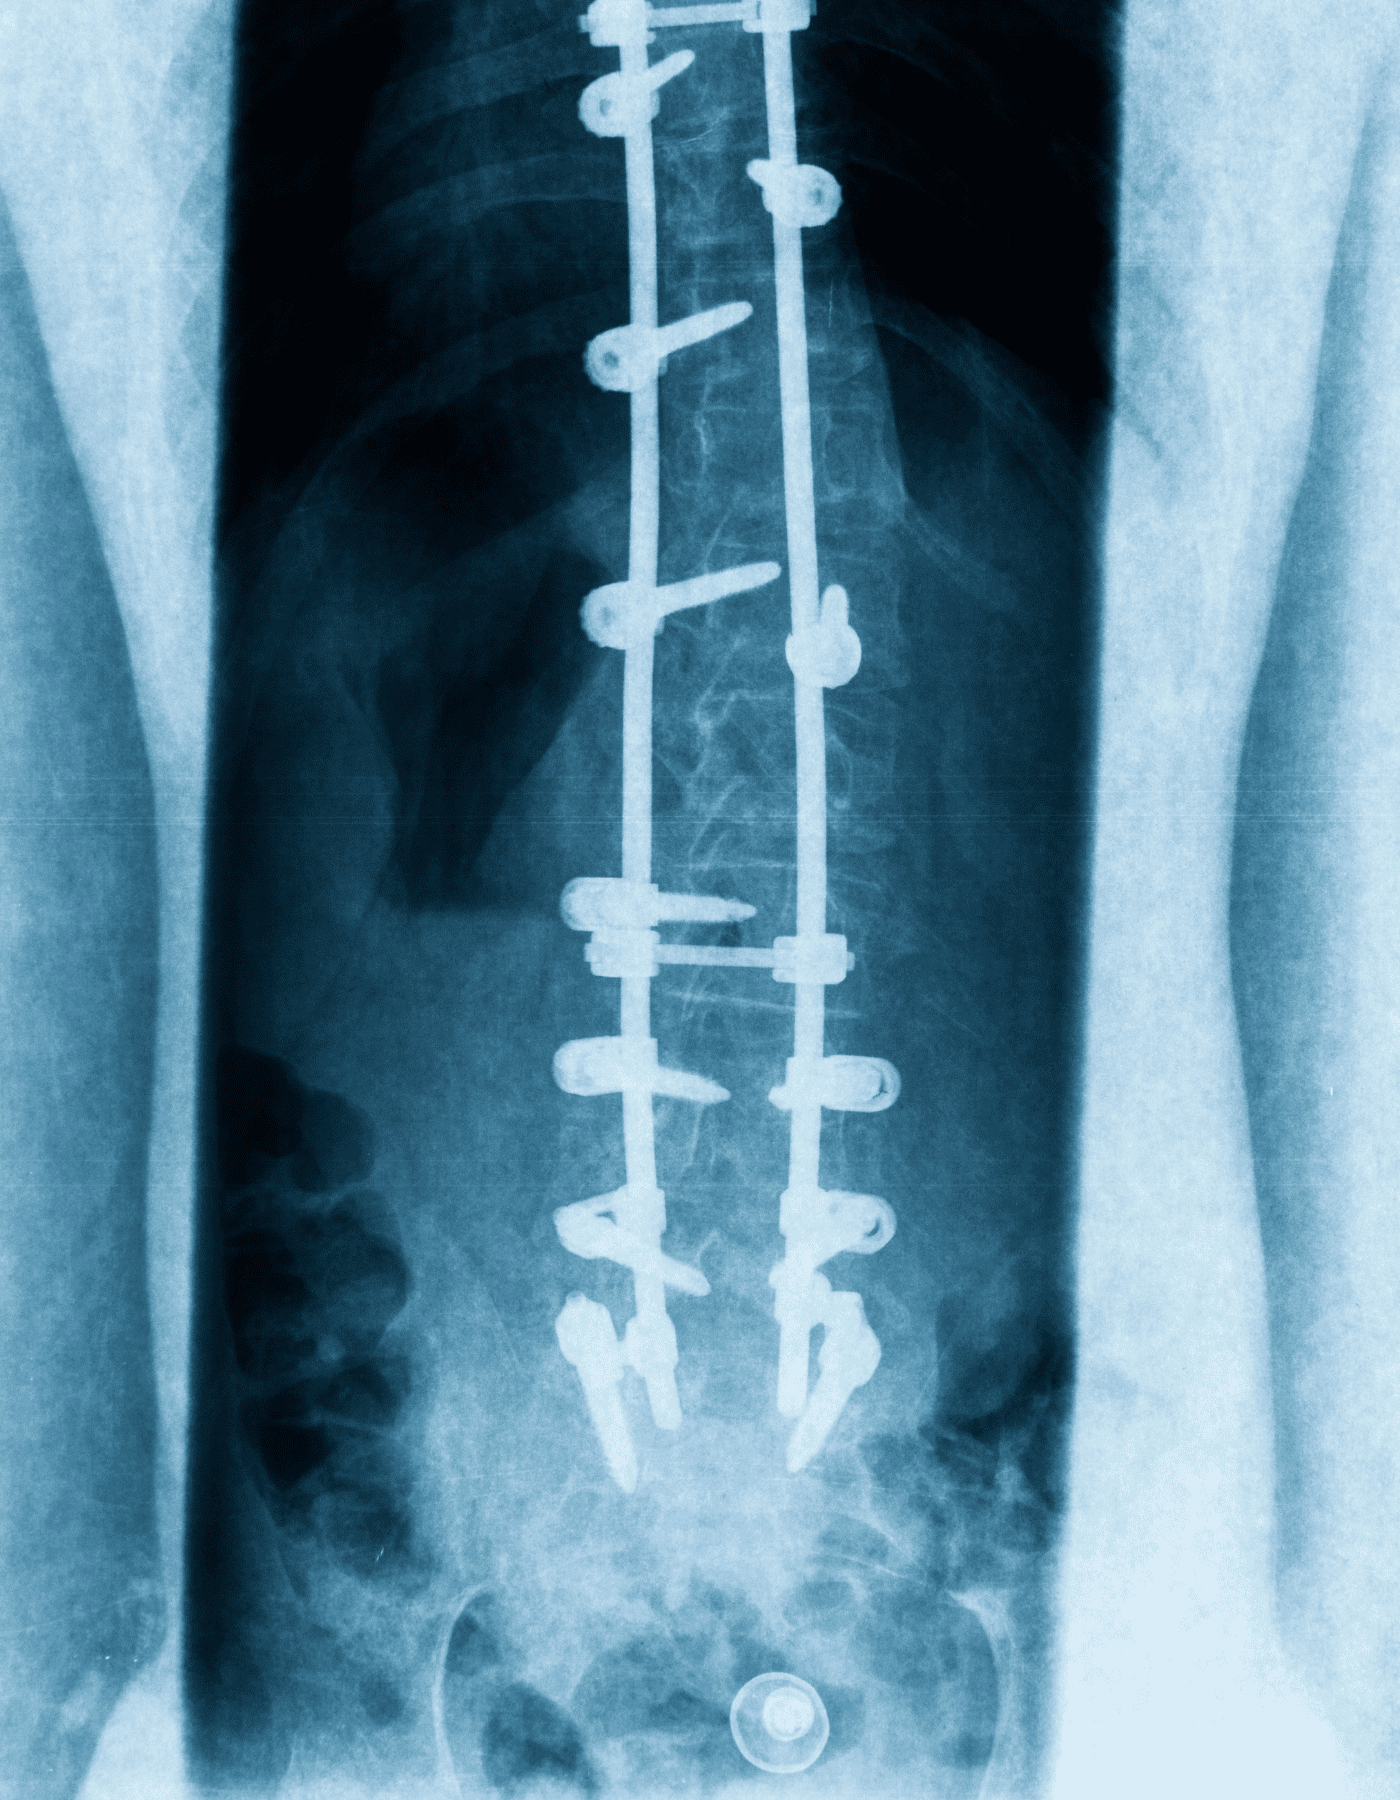

Soy médico especialista en cirugía neurológica y columna vertebral, con la experiencia profesional en el uso de la tecnología más innovadora a nivel mundial, para lograr los mejores resultados en las enfermedades del cerebro y la columna vertebral.

Soy médico especialista en cirugía neurológica y columna vertebral, con la experiencia profesional en el uso de la tecnología más innovadora a nivel mundial.